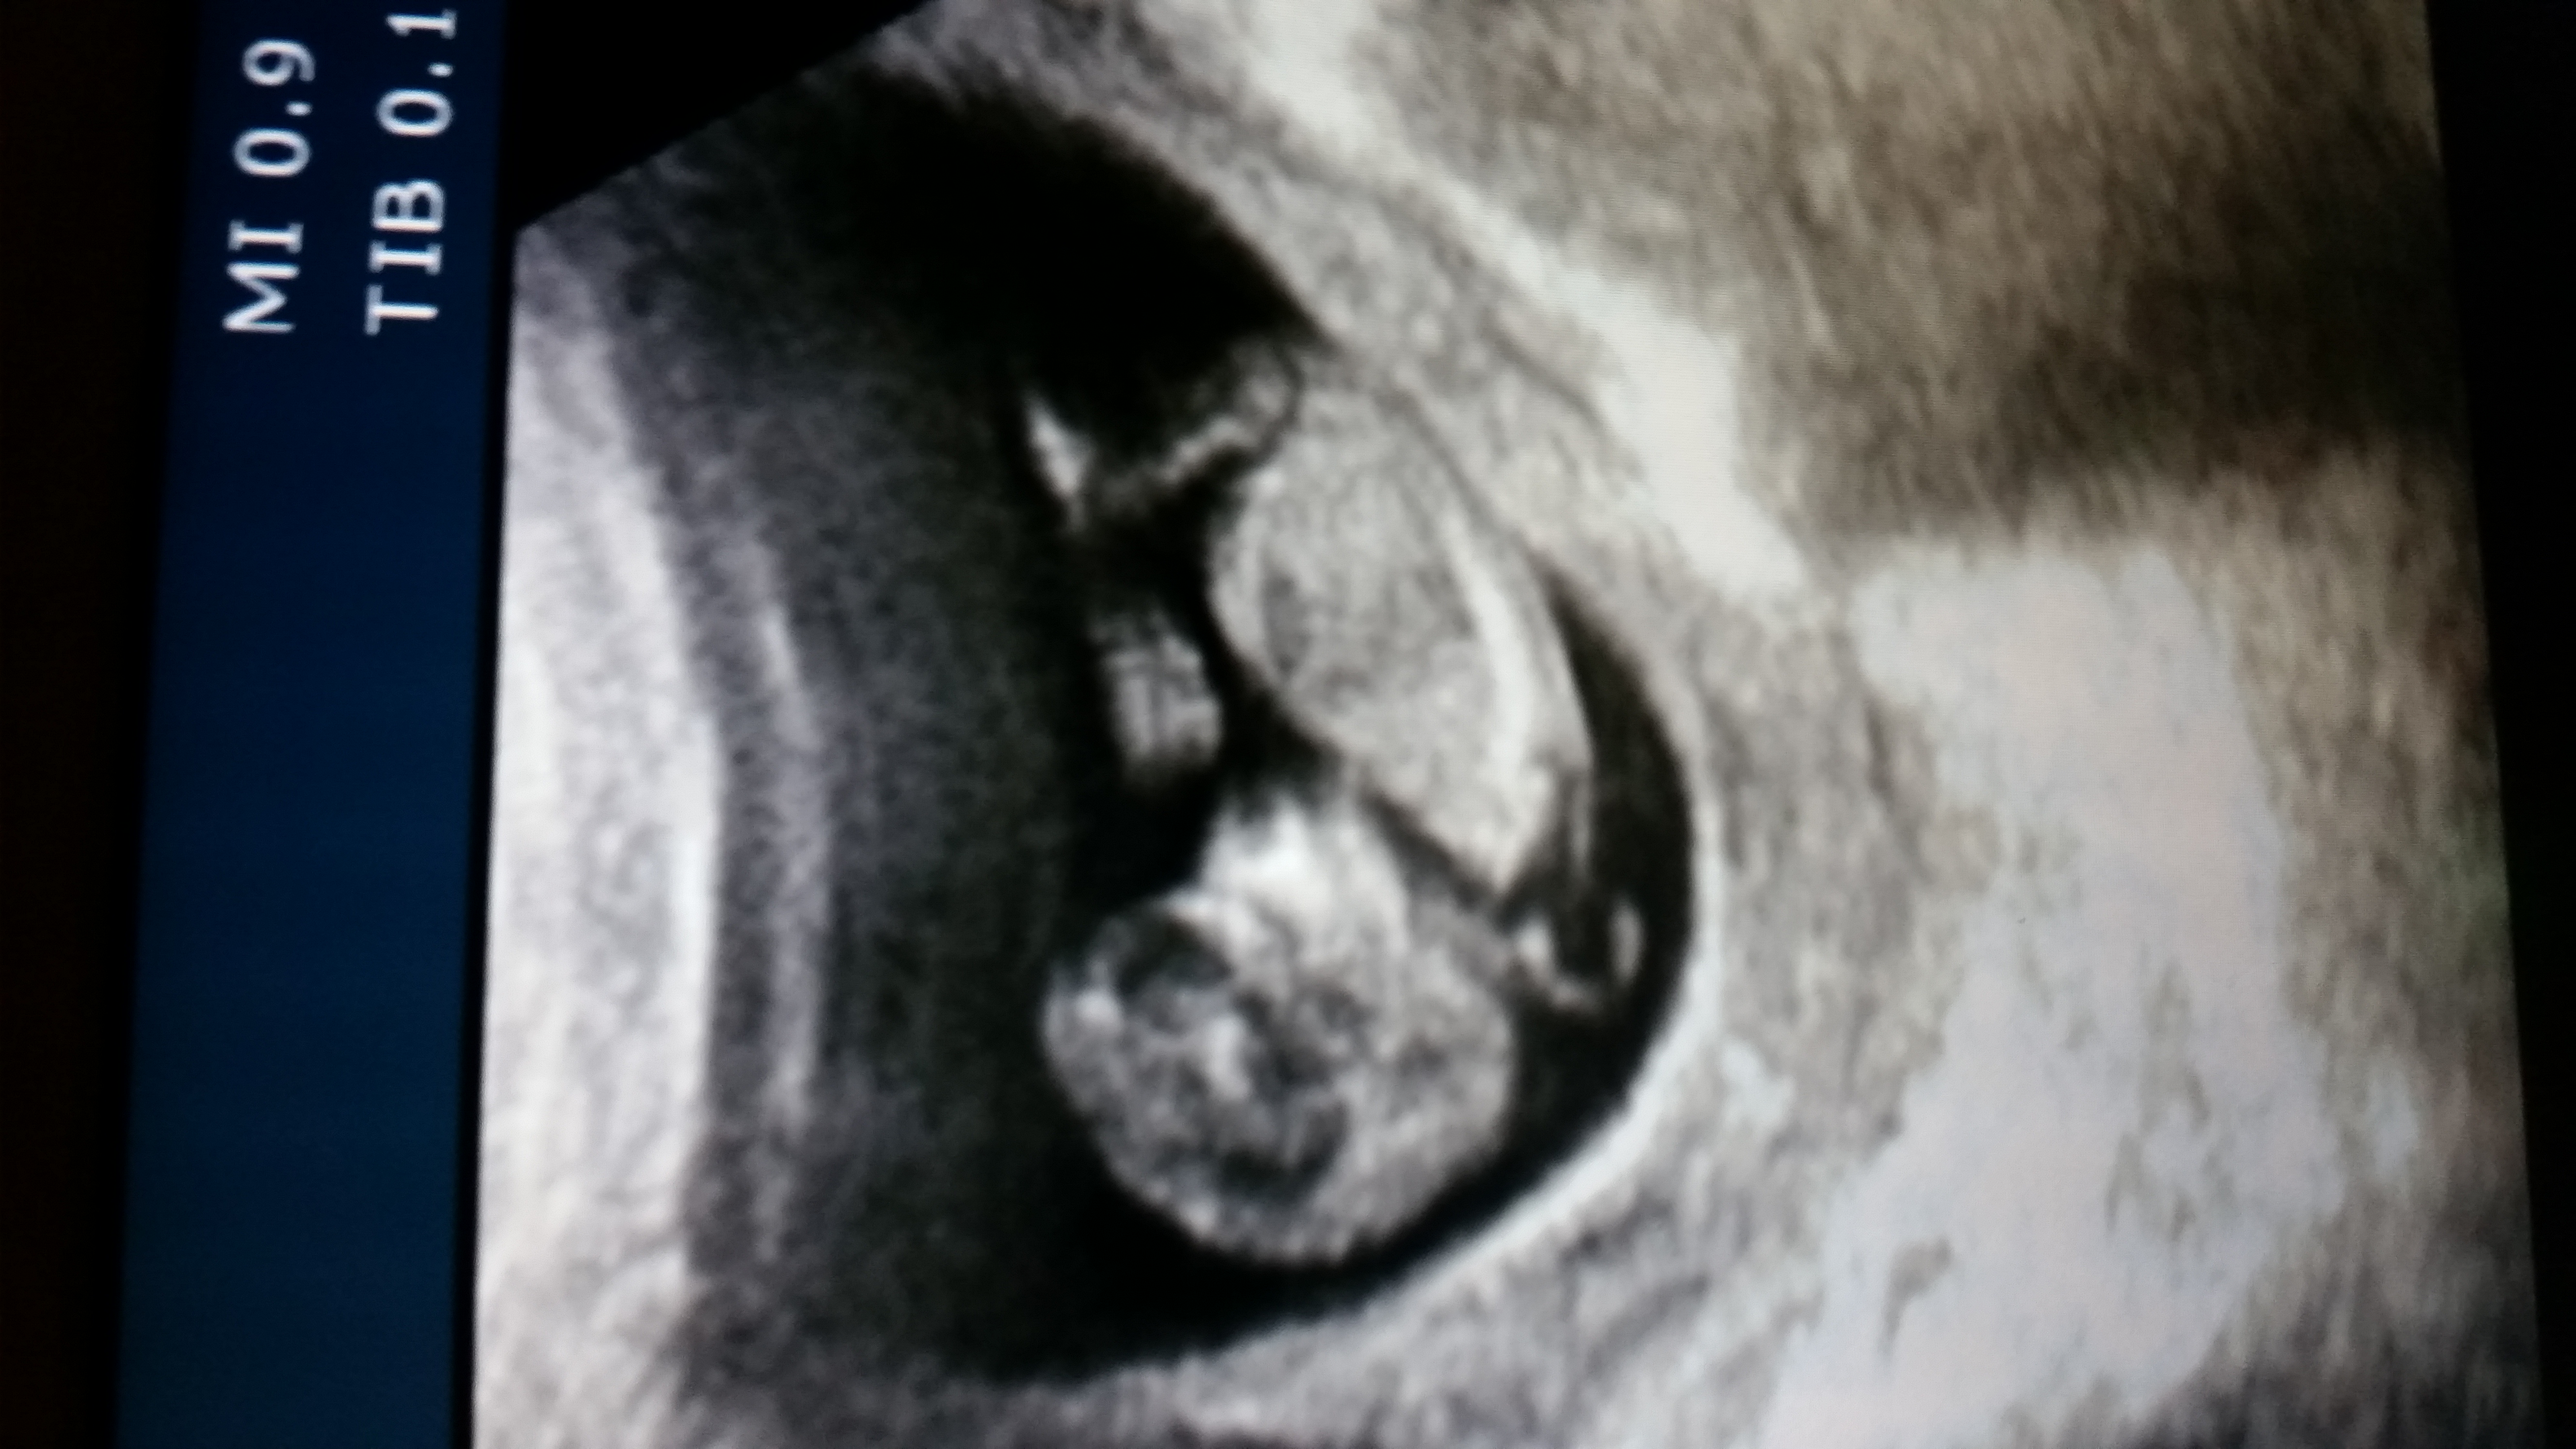

Hi there, I am so anxious to find out the sex of my baby. What do you guys think? Look at head shape and area between legs :)Attachment 22840Attachment 22841Attachment 22841

You guys are much more qualified than I am for sure lol. But am I looking TOO into between its legs? I feel as if I can see something there. It could very well be my imagination, or a bone or something of that sort.

So am I looking too into that nub shaped thing right by the leg? Call me crazy, but I see something there. Even a friend of mine had said the same thing. Or is that a bone? Lol

I see what you "think" you see and yes that is bone. Sadly no nub but a boyish skull!

Nahri thank you so much! Yes I pulled my girls ultrasound pics out and the skulls look so much different. This one was more boxed shape. And haha thank you for clarifying it is a bone LOL